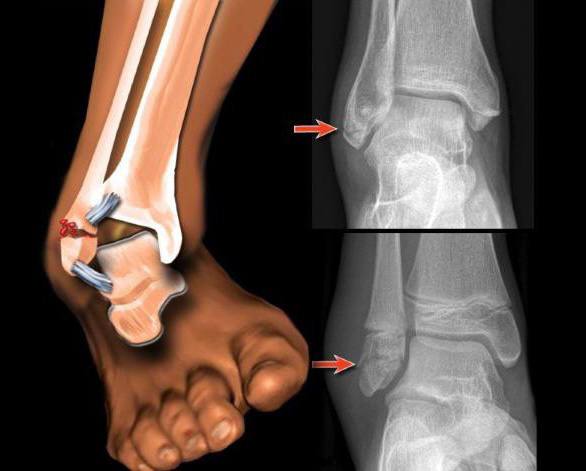

Также в сети появился рентгеновский снимок поврежденного голеностопа Неймара, согласно которому проблемы бразильца гораздо серьезнее, чем просто растяжение.

Согласно прогнозу доктора Мэтта Провеншера в интервью Fox Sports, Неймар может пропустить 1-3 недели. Это значит, что Ней пропустит оставшиеся матчи групповой стадии, первый раунд плей-офф и полностью восстановится не раньше 1/4 финала.